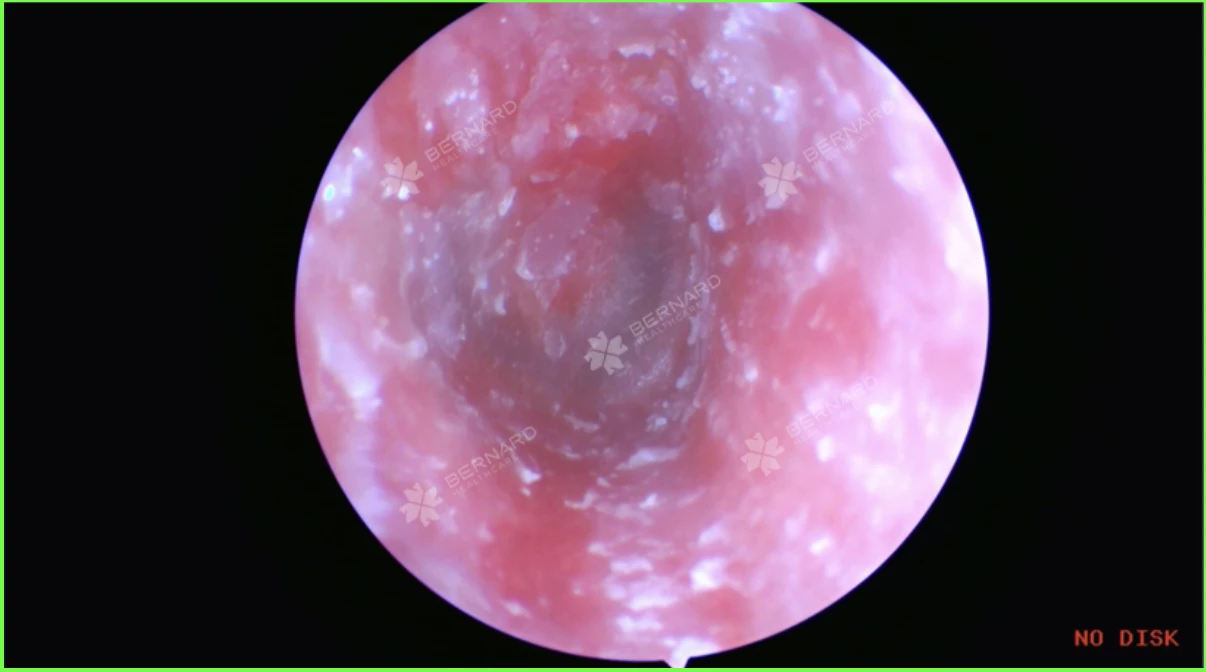

Nam khách hàng được Bác sĩ CKI. Trần Xuân Nguyên - Chuyên khoa Tai-Mũi-Họng, Bernard Healthcare trực tiếp thăm khám và chỉ định nội soi ống tai. Kết quả cho thấy, ống tai ngoài ở cả hai bên có tình trạng sung huyết, rải rác các mảng ráy tai kèm nấm. Màng nhĩ hai bên vẫn nguyên vẹn, tam giác sáng rõ, hòm nhĩ đóng ít mủ kèm nấm nhưng không đọng dịch.

- Ống tai ngoài bị trầy xước nhẹ và có các sợi nấm bám vào da bên trong.

- Ráy tai khô, không chảy dịch nhưng có ít mủ đọng, đóng mảng vảy do nấm đã làm hẹp ống tai, gây ra các triệu chứng như ngứa, đau và giảm thính lực.

Trong quá trình nội soi, bác sĩ đã tiến hành điều trị ngay tại chỗ để đảm bảo hiệu quả tốt nhất. Trước tiên, bác sĩ đã bóc tách mảng ráy tai bằng dụng cụ chuyên dụng. Sau đó, sử dụng ống hút tai thẳng kết nối với máy hút, điều chỉnh áp lực vừa phải để hút sạch dịch mủ và nấm từ thành ống tai đến màng nhĩ.

Sau khi hút sạch cặn bẩn và nấm, ống tai được rửa kỹ bằng nước muối sinh lý thông qua bơm tiêm. Trường hợp mủ đọng nhiều, bác sĩ đã bơm oxy già pha loãng với nước cất (tỷ lệ 1:3), rồi tiếp tục hút sạch cặn bã ra ngoài. Quá trình này thường được lặp lại 2-3 lần để loại bỏ hoàn toàn các chất bẩn còn sót lại.